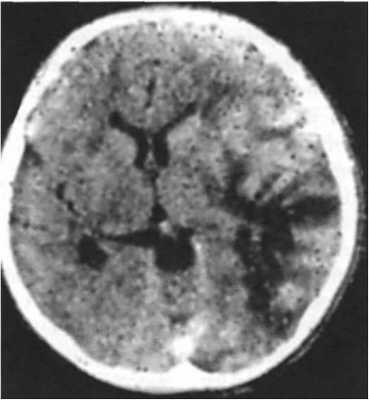

КТ

Неконтрастируемые очаги в белом веществе пониженной плотности, без отека и смещения прилежащих структур.

Очаги чаще располагаются в перивентрикулярных областях, полуовальных центрах, теменно-затылочных областях и в мозжечке.МРТ